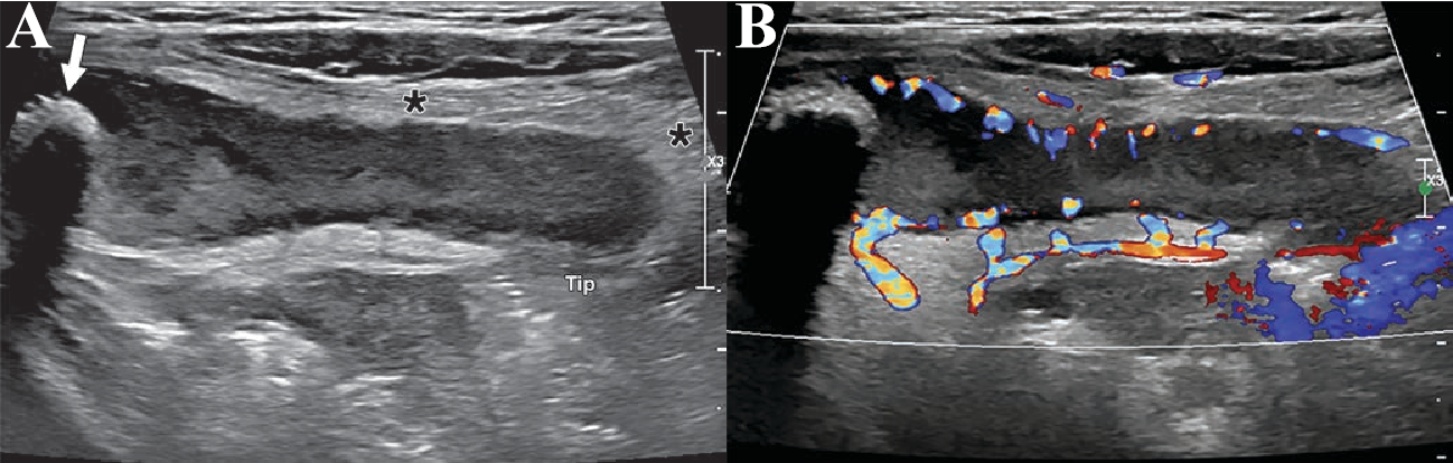

Figure 2. A 3-year-old boy presented with fever, vomiting and abdominal pain, and was ultimately diagnosed with acute appendicitis. (A) Longitudinal grayscale ultrasound image of the right lower quadrant (RLQ) shows a swollen, fluid-filled appendix with an appendicolith shadow at the base (arrow). The distal margin of the appendix is ill-defined (tip), and a microperforation was identified on histopathological sections. The surrounding adipose tissue (asterisk) exhibits increased echogenicity. (B) Corresponding longitudinal color Doppler ultrasound image of the right lower quadrant (RLQ) demonstrates hyperemia in the appendix and its surrounding tissues. The maximum outer diameter of the appendix measures 14.6 mm at the base and 10.3 mm at the tip

2. 一名3岁男孩因发热、呕吐和腹痛就诊。患者最终被诊断为急性阑尾炎。(A) 右下腹区(RLQ)的纵向灰阶超声图像显示肿胀的充满液体的阑尾,基底部有结石阴影(箭头)。远端阑尾边缘不清晰(尖端),组织学切片上发现微小穿孔。周围脂肪组织(星号)回声增强。(B) 相应的右下腹区(RLQ)的纵向彩色多普勒超声图像显示阑尾及其周围组织的高血流。阑尾的最大外径在基部测量为14.6毫米,在尖端测量为10.3毫米